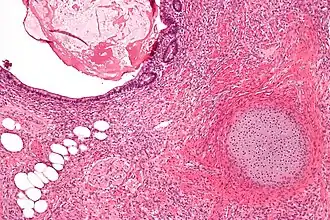

Micrografia de um teratoma com componentes gastrointestinais (direita superior) cartilagem (direita inferior) e tecido adiposo (esquerda inferior). Tingido com Hematoxilina-Eosina.

Cisto dermóide

O cisto dermóide é um dos tumores mais comuns do ovário e um exemplo de teratoma. Macroscopicamente é um tumor cístico preenchido por cabelos e material sebáceo. A parede interna do cisto tem aspecto de pele, com epiderme, folículos pilosos, glândulas sebáceas e sudoríparas. Geralmente, em uma área da parede mais saliente na luz do cisto e chamada promontório, encontramos vários outros tipos de tecido, que tipicamente derivam dos três folhetos embrionários. Alguns cistos dermóides parecem um atlas de histologia normal pela variedade de aspectos. Porém, os tecidos estão topograficamente desorganizados e agrupados sem nenhuma 'lógica'. Em diversas áreas podemos reconhecer estruturas organóides, como a que lembra víscera oca, com musculatura lisa em duas camadas e portanto ate esboço de inervação autonômica. Vemos tecido nervoso central (ectoderme) com áreas de gliose e até diferenciação para córtex cerebelar. Há vários tipos de epitélio de revestimento: escamoso, cilíndrico ciliado, com ou sem células caliciformes, e do tipo intestinal (endoderme). Há ainda glândulas mucosas, serosas e sero-mucosas (também da endoderme) e tecidos de linhagem conjuntiva como músculo liso e osso (mesoderme). Em suma, qualquer tecido normal pode estar presente.